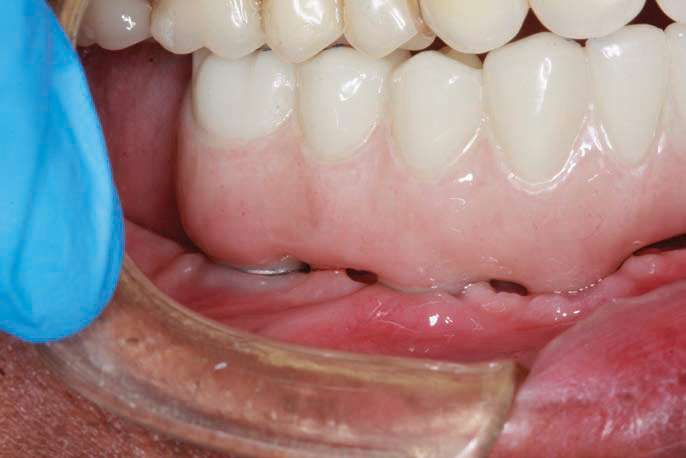

At this time, the patient suffered a stroke and lost some of the dexterity in his hands. It became evident when observing the patient’s difficulty in cleaning the PMMA provisional implant prosthesis, that he would require help from his wife. In addition, the gingival embrasures would need to be opened up more to allow for easier access with at-home cleaning aids (such as GUM Proxabrush Go-Betweens Cleaners [Sunstar Americas] and Waterpik). Instructions for these prosthetic design modifications were submitted to the dental lab, which sent updated CAD design images for clinician approval, prior to finalization of the prosthesis. After review, the digital design was modified until we had a cleansable gingival surface for the BruxZir Solid Zirconia Full-Arch Implant Prosthesis (Figures 18a to 18d). An additional PMMA provisional implant prosthesis was fabricated and delivered to confirm these final design changes; it had an almost Roman aqueduct appearance to the gingival surface of the prosthesis (Figure 19).

The final monolithic zirconia restoration was fabricated based on the same digital design as the approved PMMA provisional, allowing the patient and his wife easy access for all cleaning implements. The patient had little food impaction and was comfortable with his border movements and ability to really cut and chew his food.

The completed BruxZir Full-Arch Implant Prosthesis is the culmination of great communication with the dental lab team. The final prosthetic result ensured that the patient would not only enjoy his new bridge but would also be able to clean and maintain it with one hand (Figure 20). The relaxed smile view and postoperative Panorex (Figures 21 and 22) shows appropriate lip and tooth display and was a vast improvement over his removable lower denture. The full-face, postoperative photo (Figure 23) of the pleased patient demonstrates that the dictates of aesthetic rehabilitation were met.